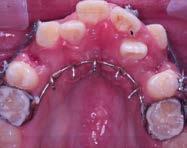

Durante la segunda cita le mostré al paciente su nuevo diseño de sonrisa en el modelo de encerado fabricado por Glidewell.

diagnóstico de alta precisión puede ser creado usando un software CAD avanzado para lograr resultados con sistentes. El técnico evalúa los dien tes a su alrededor y crea un diseño digital armonioso (Figura 3).

Cita 2. Aprobación del encerado de diagnóstico

Durante la segunda cita le mostré al paciente su nuevo diseño de sonrisa en el modelo de encerado fabricado

Después de revisar el encerado con el paciente, usé una matriz putty pro porcionada por el laboratorio para transferir el diseño a sus dientes y crear un mockup, lo que le permitió experimentar cómo se vería y senti ría la restauración final. Usando un material provisional, por lo general uso Luxatemp Ultra (DMG America;

por Glidewell, permitiéndole exami nar el diseño estético de la restaura ción final propuesta (Figura 4).

3 4

Ridgfield Park, N.J.) o TuffTemp™ Plus (PULPDENT; Watertown, Mass.), rellené la matriz putty y cemento sobre las piezas 22-12 sin preparar. Removí el exceso de acrílico mientras el material se asentaba en la boca del paciente para reducir el tiempo que hubiera necesitado para limpiar el acrílico endurecido (Figura 5).

La matriz fue removida después de que el material del mockup se asen tó. Se pueden realizar pequeños ajus tes en este punto de ser necesario. El mockup intraoral nos dio la oportu nidad, tanto a mí como a mi pacien te, de revisar la estética, fonética y el funcionamiento general del diseño (Figura 6).

Después de que el paciente hubie ra aprobado su nueva sonrisa, reali cé un escaneo intraoral del mockup usando un software iTero. Este “pre escaneo”, como se le conoce, es una imagen que se envía al laboratorio para guiar a los técnicos dentales al diseñar las restauraciones finales (Figura 7).